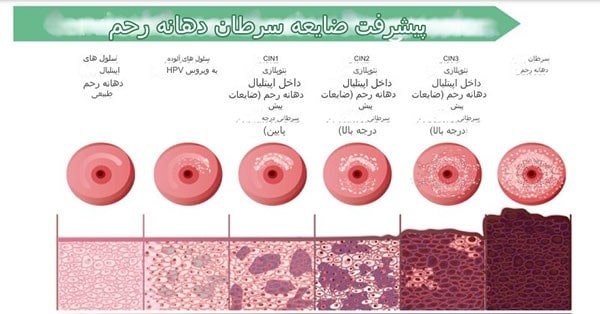

کولپوسکوپی زمانی انجام می شود که نتایج آزمایش های غربالگری سرطان دهانه رحم یعنی همان تست پاپ اسمیر تغییرات غیر طبیعی در سلول های دهانه رحم را نشان دهد. کولپوسکوپی اطلاعات بیشتری در مورد سلول های غیر طبیعی ارائه می دهد. در صورت ابتلا به انواع خاصی از ویروس زگیل تناسلی یل پاپیلومای انسانی (HPV) کولپوسکوپی نیز انجام شود.

-دیسپلازی دهانه رحم (تغییرات پیش سرطانی در بافت دهانه رحم).

-سرطان دهانه رحم.

-سرطان دهانه رحم: نوعی سرطان که در دهانه رحم یا سرویکس ایجاد می شود. دهانه رحم در بالای واژن قرار دارد.